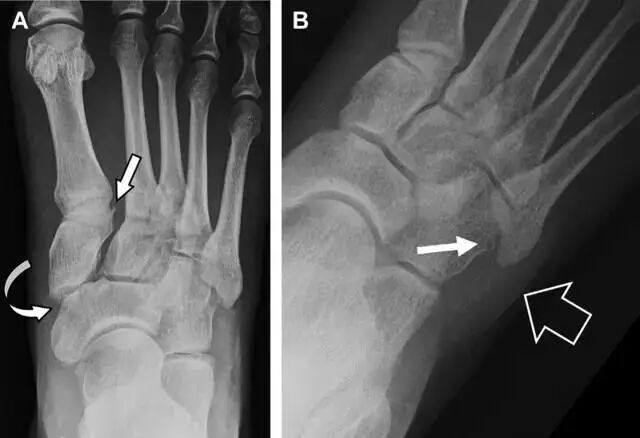

跗跖关节复合体(Lisfranc 关节复合体)损伤

与跗跖关节韧带相关的骨折常由旋前或旋后的跖屈损伤引起。尽管跗跖关节骨折脱位仅占所有骨折的 0.2%,但是约 20% 的这些骨折在初次检查时被漏诊。初次 X 片可能示正常,但是负重位 X 线片常常提示脱位或半脱位。

典型表现:第二跖骨底和内侧楔骨之间的骨折碎片,跖骨间间隙增宽(图 8)。脱位亦可发生在舟骨-内侧楔骨关节,导致另一种变异的跗跖关节损伤(图 9A)。此外,骰骨的小块皮质撕脱在足部斜位片上可清晰显示(图 9B)。

图 9 变异的跗跖关节骨折。A  另一种类型的跗跖关节损伤,中间楔骨向内侧半脱位(弧形箭头),从而使第一、第二跖骨间间隙变宽,需注意,骨折在靠近内侧楔骨处(箭头);B 外侧跗跖关节损伤伴随从骰骨跖骨韧带的骰骨撕脱(箭头),需注意,第五跖骨底近端处存在软组织水肿(空箭头)